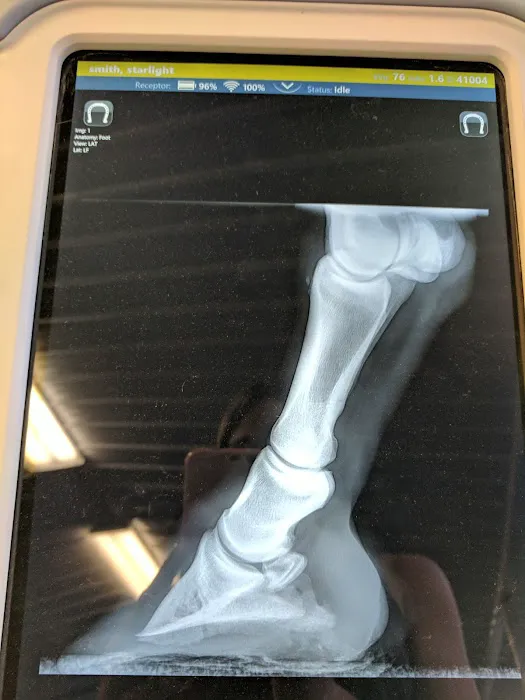

- Diagnostics: In-House Bloodwork Machines, Heartworm Testing, Fecal Exam/Parasite Screening, Digital Radiographs, Ultrasound, Cytology/Biopsy Sampling, Urinalysis, Culture/Sensitivity Testing, and comprehensive Eye Exams and Skin Scraping.

- Advanced Diagnostic Tools: The availability of in-house bloodwork machines, digital radiographs, and ultrasound technology allows for rapid and precise diagnosis, which is crucial for timely treatment.

May 11 · Carly CaronDr. King and his team took excellent care of my mare and helped me figure out why she's been lame. They were thorough, professional, have a fantastic facility and have incredibly reasonable prices!! He's not one of those vets that explains everything he's doing step by step, but if you wait patiently till the end of his evaluation and/or treatment he will explain everything to you in detail. He does not make farm call, so you have to be able to transport your horses to him, but the effort and time is well worth it!!